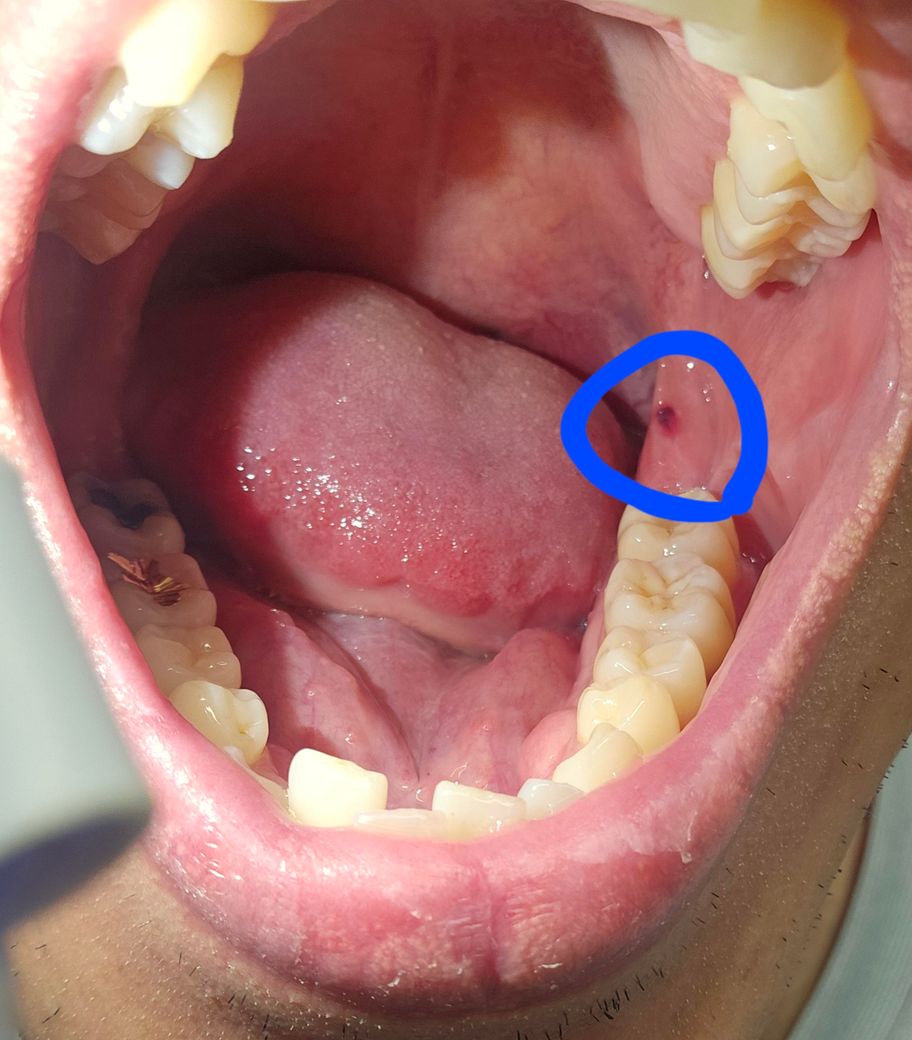

입 안에 피 멍울 같은게 생겼는데 이게 뭘까요?

양치질을 하다보니 입 안에 피 멍울 같은게 생겼더라고요.

• 1번 째 사진

볼살이 치아에 씹히면서 피가 고인겁니다. 그냥 터트리시거나 그냥두셔도 시간이 지나면 괜찮아 지실꺼에요.

해당 부분은 볼을 씹어서 생긴 혈종이 의심됩니다. 보통은 시간이 지나면 사라지는 편 입니다

구강혈종으로 보이며, 혈관이 터지면서 입안의 점막 아래에 피가고이는 증상으로 보통은 치료를 하지 않아도 1-2주내로 저절로 없어지게 됩니다.

사진으로 보이는 멍울은 점막조직이 외부 자극으로 인해서 출혈이 되고 점막조직에 혈액이 차게 되어 생기는 혈종으로 보입니다.

크게 문제가 되지 않으며 대부분 시간이 지나면서 점차 없어지게 됩니다.

혈종의 양상인데 보통은 1~2주면 자연스럽게 사라집니다. 그 이상 남아있거나 통증이 있으면 구강내과가보시기 바랍니다.